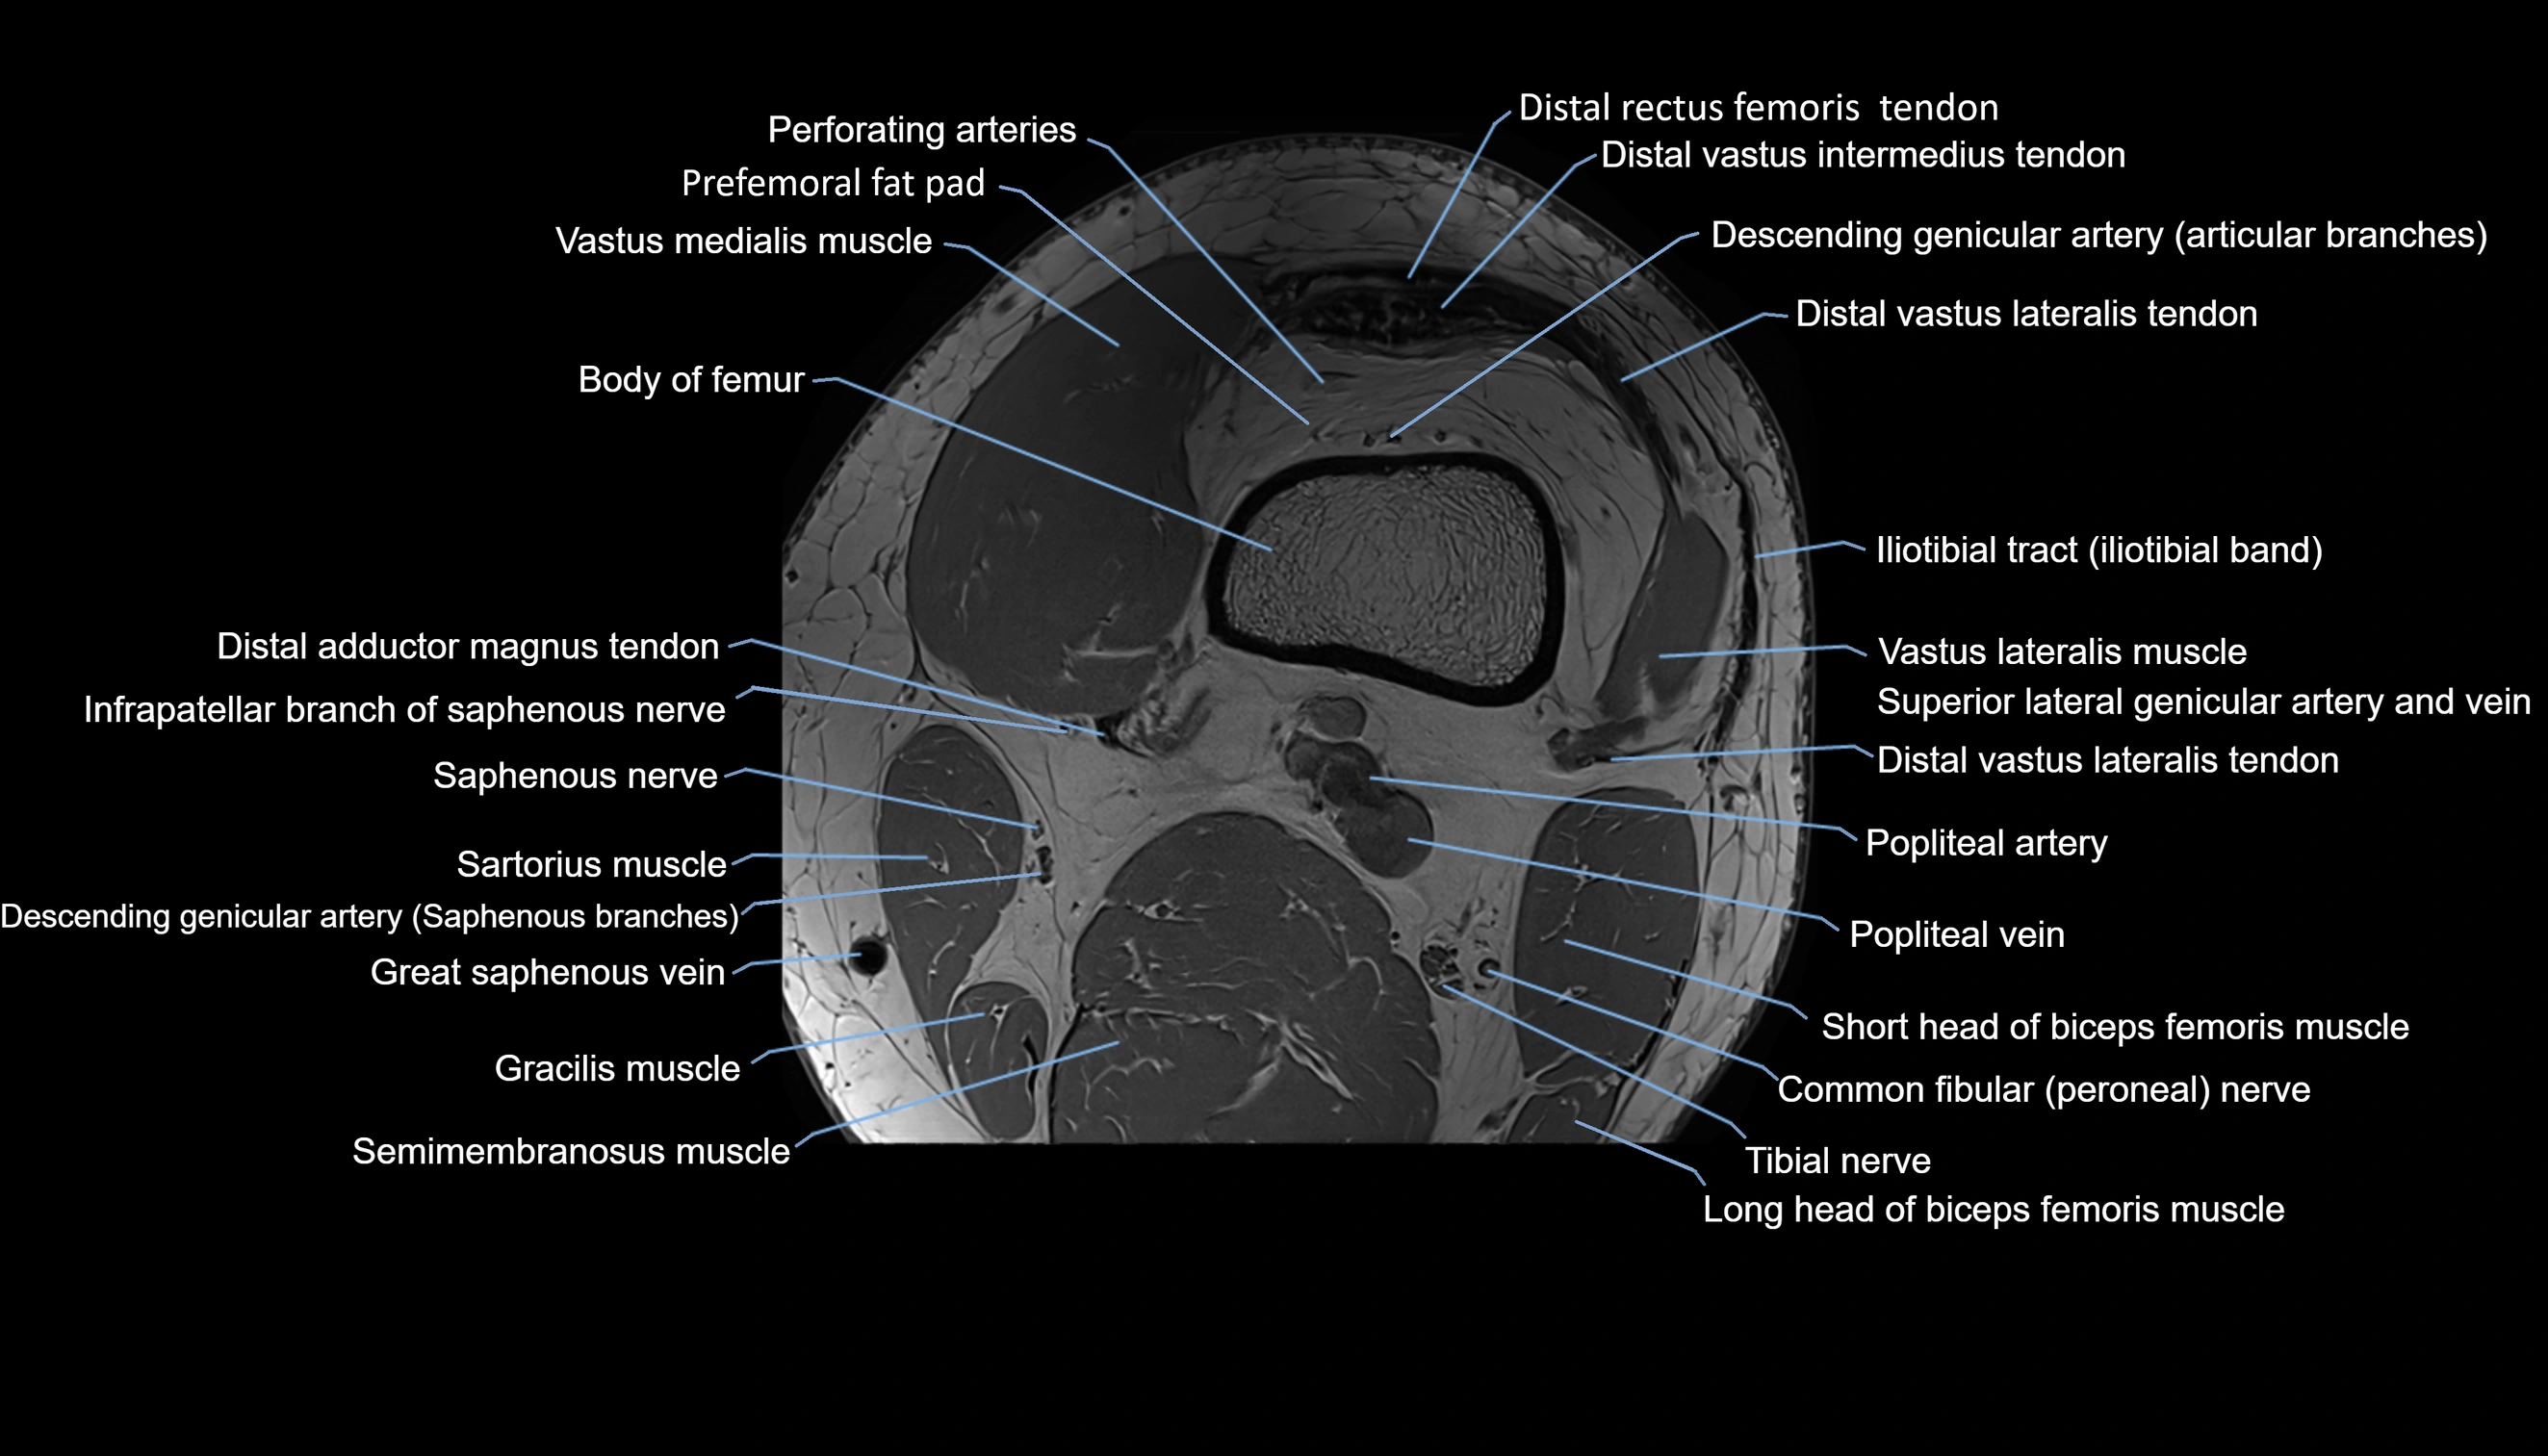

- Body of femur

- Descending genicular artery (Articular branches)

- Distal adductor magnus tendon

- Distal rectus femoris tendon

- Distal vastus intermedius tendon

- Distal vastus lateralis tendon

- Perforating Arteries (Knee joint)

- Popliteal artery

- Popliteal vein

- Saphenous nerve

- Sartorius muscle

- Semimembranosus muscle

- Superior lateral genicular artery

- Superior lateral genicular vein

- Vastus lateralis muscle

- Vastus medialis muscle

- great saphenous vein